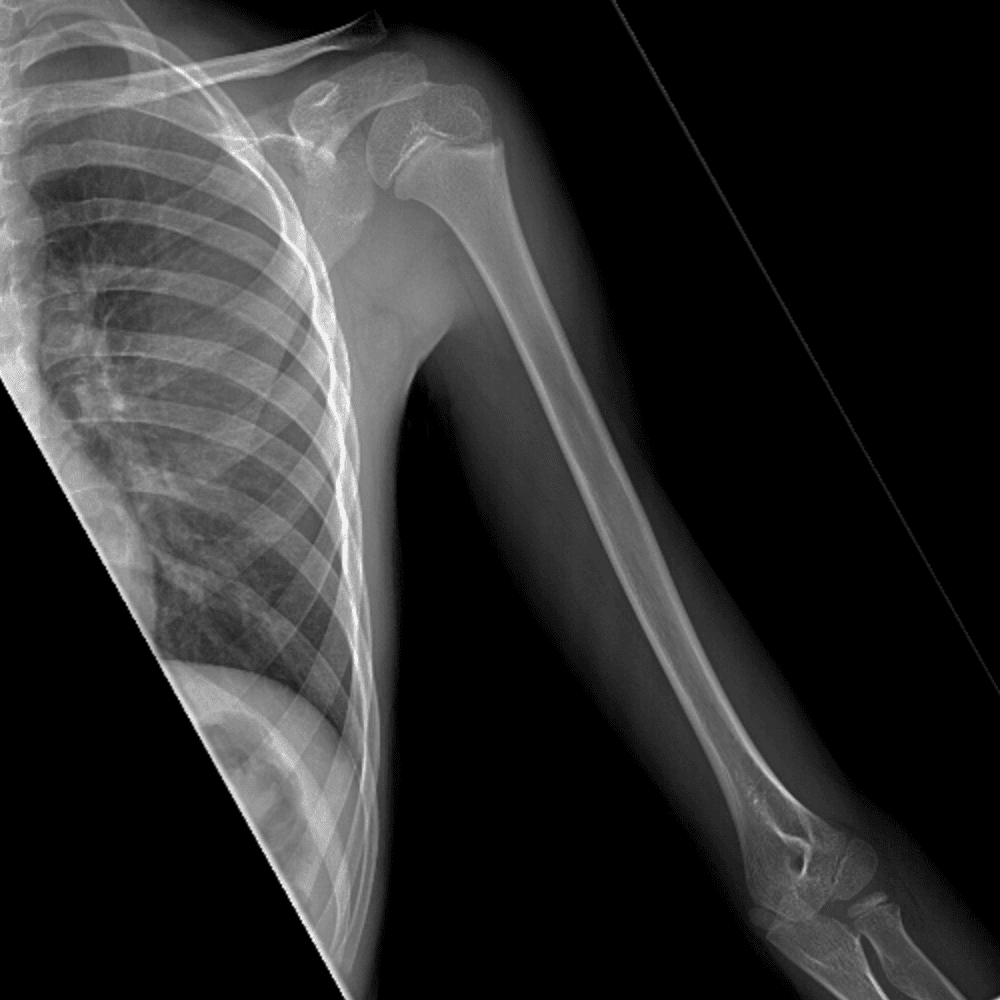

Simuliert den Dienst durch subtile oder schwierige Fälle und einige Normalbefunde.

30 Fälle